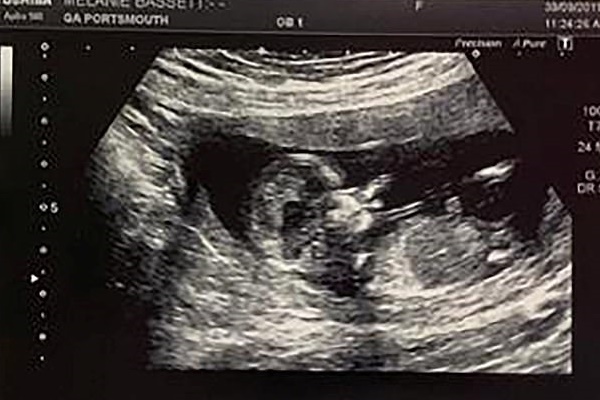

Hình ảnh siêu âm thai nhi con gái của Samantha Spicer (34 tuổi, đến từ Rushden, Northamptonshire, Anh).

"Những khoảng sáng trên màn hình siêu âm đã tạo ra hình ảnh giống như một chiếc khẩu trang trên khuôn mặt của con gái tôi. Ngay khi siêu âm, các bác sĩ ở đây và tôi đã cười lớn. Hình ảnh đó thật sự rõ ràng.

Trong một hình ảnh khác được thể hiện trên màn hình siêu âm, các bác sĩ và Samantha còn nhìn thấy được cô bé như đang giơ tay để vẫy chào mọi người.